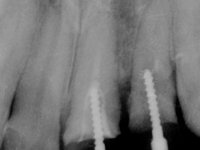

Patient male, 60 years old, non-smoker. After imaging and clinical examination, it was found that the patient had teeth 2.1 and 2.2 with extensive acrylic restorations, with screwed intra radicular posts and very poor endodontic treatments. Tooth 2.2 had an extensive apical lesion, the post had been placed on a false route and had mobility. Tooth 1.1 had an extensive resine restoration and tooth 1.2 presented a mesial restoration, also in composite resin, Class III type. The antero-superior sector was vestibularized, as consequence of a loss of vertical occlusion dimension associated with posterior edentulism. The patient showed reasonable periodontal health and satisfactory oral hygiene.

Endodontic treatments were performed and a metalic non screwed intra radicular post was placed on tooth 1.1. An alginate impression was made for laboratory confection of a reinforced acrylic provisional bridge, with teeth 1.1 and 2.2 as abutments and 2.2 as a pontic. After preparation of tooth 1.1 and root preparation of 2.1, the bridge was relined in mouth with self-polymerizable acrylic using a metal post for further retaining the prepared root canal on 2.1. Tooth 2.2 was cut at the gingival level to function as support. In the same session, the impression of the root canal of the 2.1 was made for the laboratory confection of a cast post and core. A double mixture technique with plastic tutor was used after previous canal vaseline with endodontic file and cotton. The provisional bridge was provisionally cemented and the cast post and core was made in the laboratory. Cast post and core cementation was made with resin-reinforced glass ionomer cement and the provisional bridge had to be readjusted to the new situation by removing the post at the site of 2.1. After careful surgical planning, a dental implant was placed, simultaneously with extraction of the root of tooth 2.2. The provisional bridge was placed by resting on the healing screw placed in the implant. The respected osteointegration period was 12 weeks, during which the provisional bridge was relined twice. After complete maturation of hard and soft tissues, definitive impressions were made. The gingival retraction technique was applied with an impregnated retraction cord and impression was performed using double mixture, open tray impression technique. A custom precious metal abutment implant was prepared in the lab, along with 3 metal caps to be used as infrastructures for the metal ceramic crowns. Particular care was taken in the confection of the cervical finishing line of the implant abutment, in order to follow the soft tissues emergence profile. Proof of infrastructures was done in the mouth being evaluated clinically and imagiologically. Collection of color information was done by the ceramist at the office. Ceramic was applied in the laboratory and the finished work was placed in the mouth after approval by the patient. Definitive cementation was made with resin-reinforced glass ionomer cement, and the first crown to be cemented was that of the implant, to facilitate removal of the excess.